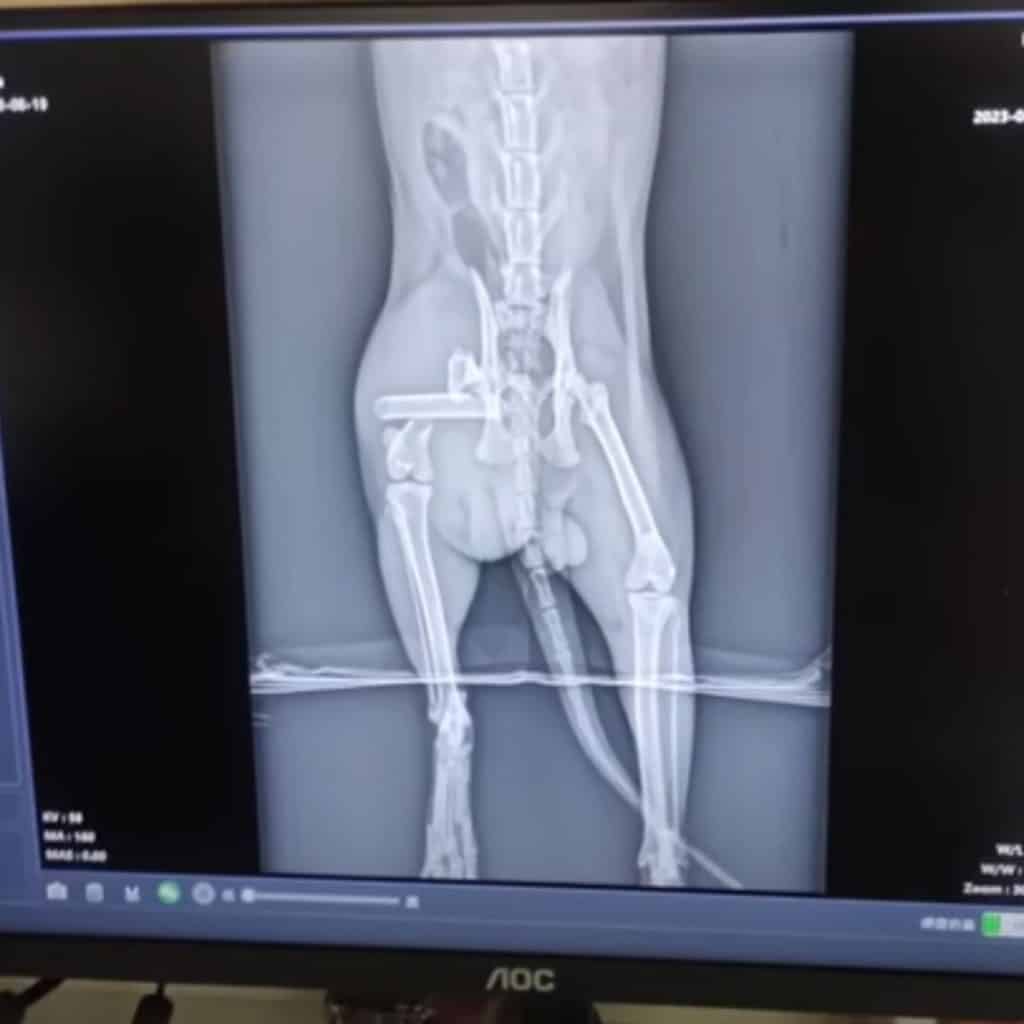

But the examination painted a grim picture. Not only was he completely infested, but X-rays showed multiple fractures in one leg — injuries that would require major surgery if he had any chance of walking again. Even the vet looked worried.